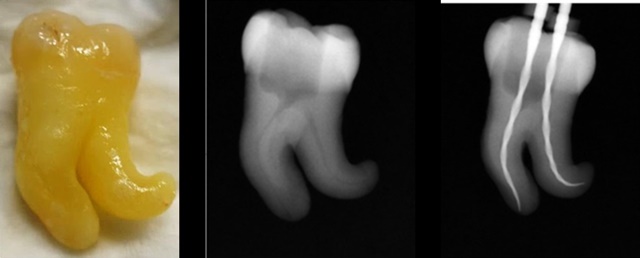

RECIPROC blue는 기존 레시프록 대비 유연성 40% 이상, 파절 저항성도 2.3배 증가하면서 만곡 근관 적용 범위 확대는 물론 파절에 대한 시술 안전성을 강화시켰다. 더불어 기존 파일보다 10도의 형상 기억 각도가 증가하면서 근관에 Transportation, Zip 현상을 방지하고, 근관 치료 성공률을 제고시킬 수 있다. 아울러 파일을 근관 방향으로 구부리는 Pre-bent가 가능해 근관내에서 길을 잘못 형성(Ledge) 하였더라도 마무리가 가능하다.

기존 레시프록의 원파일 시스템을 그대로 계승한 RECIPROC blue는 대부분의 복잡한 근관도 R25 파일 하나로 성형이 가능하다. 보통의 원파일로 소개되는 여타의 시스템이나 전통적인 스테인리스 스틸 핸드 파일의 경우 일부 단점들이 존재해왔다. 다양한 핸드 파일과 드릴 사용 요구, 많은 시간 소요, 근관 변위 발생율 증가, 그리고 핸드 인스트루먼트를 협소한 근관에 적용시 접근이 어려운 치아 치료는 매우 취약하다는 것이다. Reciproc blue는 근관 성형 완성까지 진정한 ‘원파일’을 구현한다.

임상적으로 검증된 S-Shaped 디자인을 적용한 것도 RECIPROC blue의 빼놓을 수 없는 장점이다. S-Shaped 디자인의 특징은 날 삭제에 있어 강력한 삭제력과 타 파일 대비 작은 코어로 인한 유연성, 삭제편의 배출공간이 충분하다는 점이다. S-Shaped의 우수한 디자인은 2세대 전 로터리파일인 Mtwo부터 레시프록을 거쳐 RECIPROC blue에도 적용됐다. 이로인해 시중 파일들이 적용하기 힘든 더 어려운 근관 케이스에도 손쉽게 특화했다.